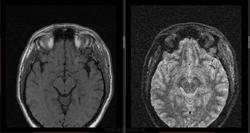

- https://radiomed.ru/sites/default/files/styles/case_slider_image/public/user/16807/7_5.jpg?itok=rB786yvP

- https://radiomed.ru/sites/default/files/styles/case_slider_image/public/user/16807/9_2.jpg?itok=dLUwi9M9